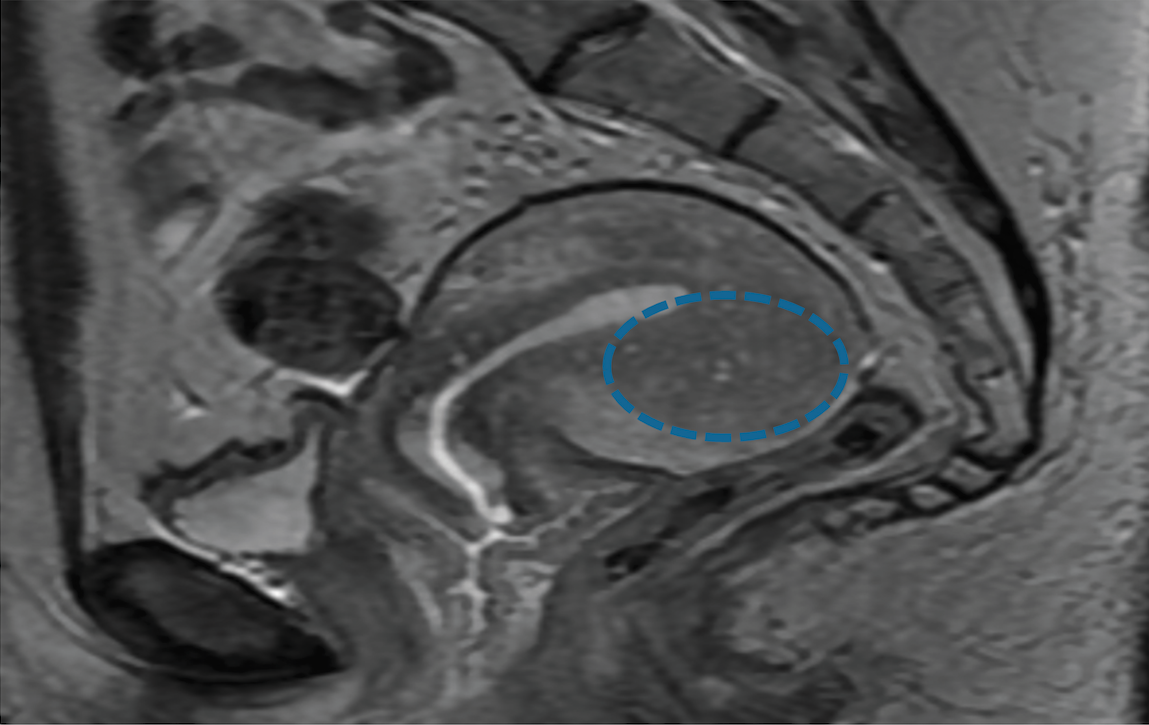

A recent study determined that magnetic resonance imaging (MRI) and rectal endoscopic sonography (RES) are of significant, but different value in determining the presence and depth of deep infiltrating endometriosis (DIE).